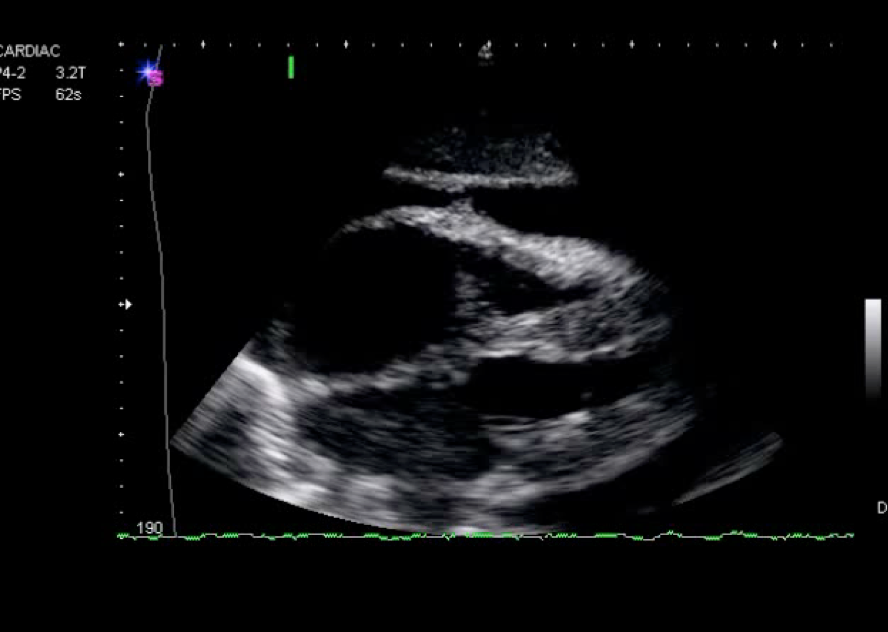

What happened to this driver in an MVA?

Pericardial effusion